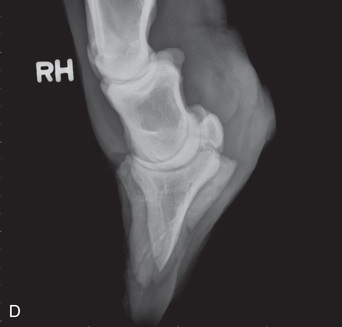

Digit/foot: P-III (distal phalanx, coffin bone) P-II (middle phalanx) P-I (proximal phalanx-pastern) Proximal interphalangeal joint (pastern joint) joint | DP (Standard) (Fig. 24.62B,C) | Dorsal 45-degree proximal–palmarodistal (D45Pr-PaDi) | Foot slightly forward on image receptor. | Perpendicular to foot axis at MSP (midsagittal plane) at area of interest with beam angled ~45 degrees to ground |

| Lateral (Standard) (Fig. 24.62D) | Lateromedial | On a block to elevate limb for P-III; resting on ground for other views. | 90 degrees lateral to MSP, parallel to ground on area of interest: coronary band for PIII | |